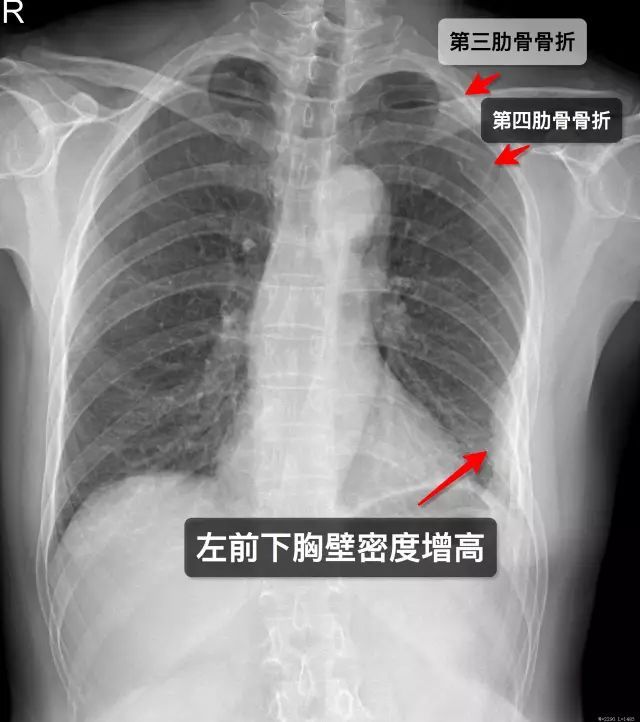

那些年,你漏诊过的肋骨骨折!

肋骨骨折

肋骨骨折图片x光

肋骨骨折x光片

肋骨骨折胸片